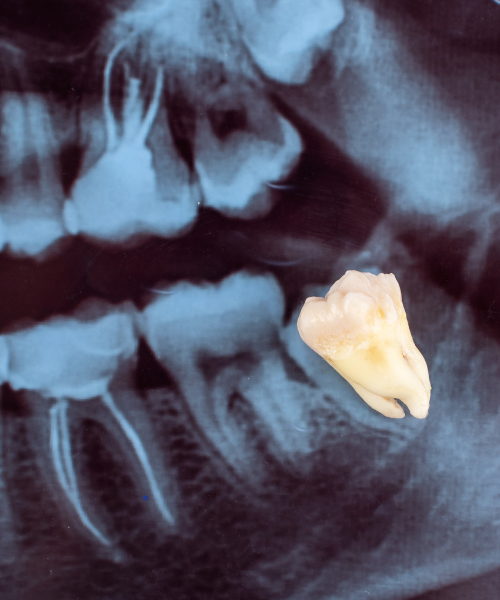

Consultation & X-ray – We first examine your tooth and take an X-ray to understand the exact condition.

Gentle Extraction – Using modern instruments, the tooth is carefully removed.

Simple Extraction – For visible teeth that are loose or damaged

Surgical Extraction – For teeth that are broken, hidden under the gums, or impacted

Wisdom Tooth Extraction – For wisdom teeth that cause pain, swelling, or infection